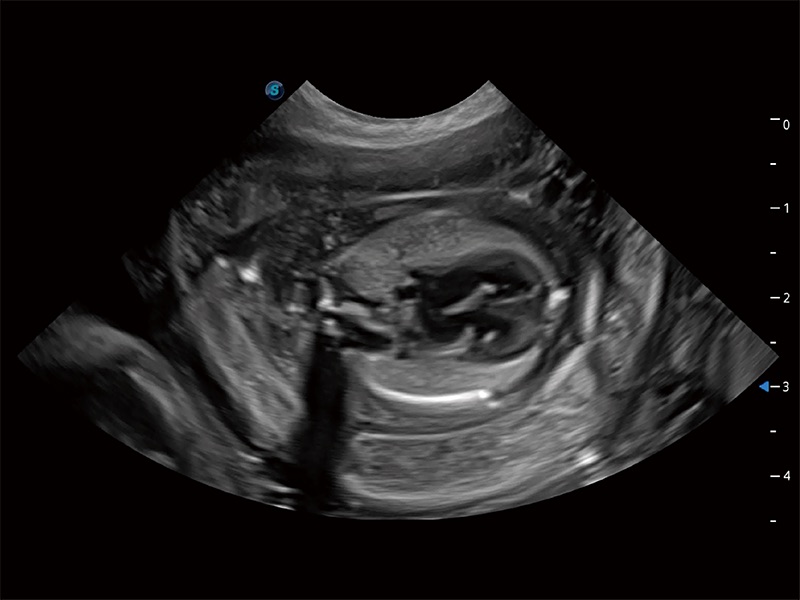

动物是人类最亲密的朋友和最值得信赖的伙伴。新葡的京集团8814检测站也一直致力于探索动物专用的超声影像解决方案。全新推出的ProPet系列,是新葡的京集团8814检测站在动物超声影像智能化、专业化、精准化的一次跨越式革新。动物不能用言语来表述自己的不适,通过超声影像,ProPet系列搭建了动物医生与不同物种沟通的“桥梁”,为动物医生注入了“治愈之力”。 ProPet 80 是新葡的京集团8814检测站匠心打造的一款高端动物专用彩超,采用性能卓越的全新硬件架构,极大提升超声系统的运行效率和数据处理能力,帮助动物医生从容应对日益增多的挑战性病例和日益多样化的临床需求。

高性能和先进的临床应用工具可以为动物医生提供临床信心。ProPet 80 搭载了先进的腹部和浅表应用工具,帮助医生在日常临床实践中发挥前所未有的作用。

ProPet 80 全新的动物超声智能软件和丰富的探头群,为动物医生提供了高清晰度和精细分辨率的图像,无论在宠物、马科、畜牧还是实验室动物等应用中都可以轻松应对,为您的日常工作带来满意的体验。